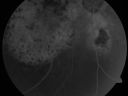

Pigmented Choroidal Mass Right Eye - Melanoma vs. Nevus vs. Unilateral Melanocytic Proliferation - 4 Month Follow-Up Images692 views71-year-old man his vision 4 month follow-up. Vision is 20/60 and patient sees flashing lights. Lesion has grown slightly in the superior half of the macula.     (0 votes)

PHOTOGRAPHS: Photos confirm clinical findings.

FLUORESCEIN ANGIOGRAPHY: The right eye shows hyperfluorescence corresponding to a window defect overlying the nevus. The choroidal vasculature can be easily seen throughout the area in a dependent fashion, suggestive of chronic subretinal fluid. There is also hyperfluorescence inferior to the optic nerve with hypofluorescence over the area of geographic atrophy. There is some stippled hyperfluorescence within the lesion in the late frame. The hyperfluorescence in general fades in the late frames. There is no evidence of any active leakage. The drusen over the surface of the nevus inferonasal to the optic nerve, which is overall dark, do stain in the late frames as well. The left eye is angiographically normal throughout the studies.